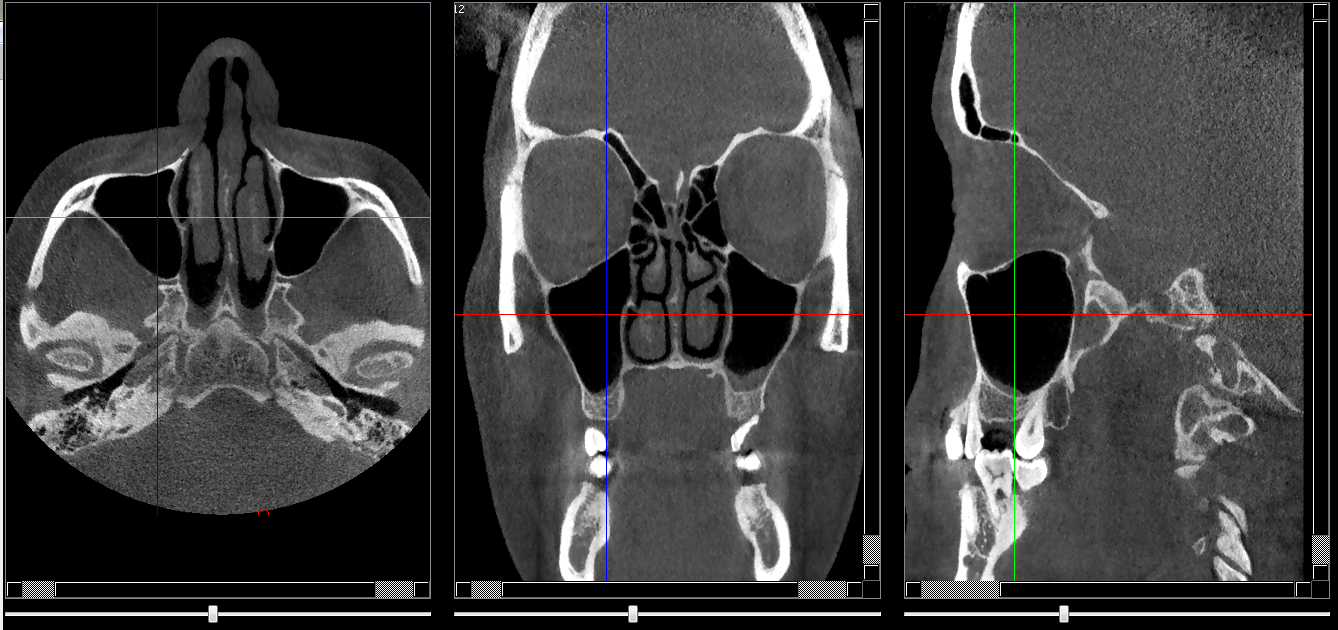

Structures osseuses

sinus maxillaire

Repères anatomiques

Coupe transversale

• Début      : Procès alvéolaire des dents antrales

• Fin             : Plancher des orbites

Coupe frontale

• Début      : Derriére la partie cutanée des joues

• Fin             : Corps du sphénoide

Coupe saggitale

• Début      : Processus zygomatique

• Fin             : Début du cornet nasal inf et moy